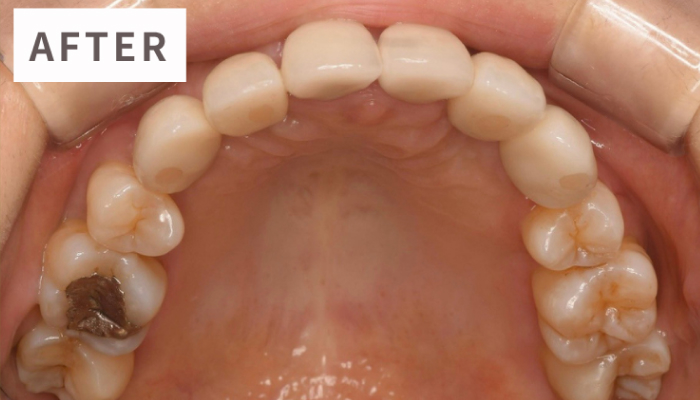

インプラント治療は「第二の永久歯」とも呼ばれる、失われた歯の代替として、顎の骨にチタン製の人工歯根(インプラント)を埋め込み、その上にセラミック製の人工歯を取り付けることで、咬む機能や見た目を回復する治療法です。顎の骨とインプラントがしっかりと結合するため、天然歯とほぼ変わらない安定した噛み心地を得ることができます。

精密インプラント治療All-on-4(オールオンフォー)インプラント治療は、少ない本数のインプラント(片顎4~6本)で、噛む力を即日回復させる画期的な治療法です。従来、多くの歯を失うとインプラントの本数や費用が増え、治療後も数ヶ月は仮歯を装着できませんでした。しかし、All-on-4では治療当日に仮歯を固定し、軽い食事が可能になります。これにより費用や身体的負担を大幅に軽減できます。